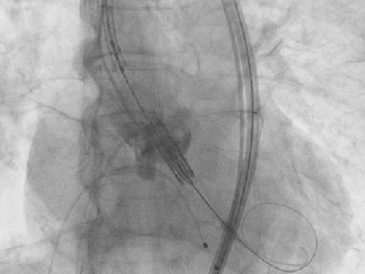

病例2:高龄、长期心功能不全

患者为70岁男性。因劳力性气喘无法活动入院。

术前检查:

超声提示主动脉瓣重度狭窄合并中度关闭不全,二尖瓣中等量反流,三尖瓣少量反流。

最终影像